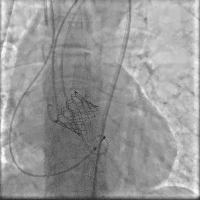

在快心室率起搏下平稳释放瓣膜,瓣膜释放过程稳定流程,瓣膜准确铆定于主动脉瓣环(视频3)。

术后造影(视频3)

停止起搏并撤回输送系统,撤出引导钢丝,关闭血管入路,术后造影及超声评价瓣膜功能良好,前向血流速度1m/s, 无明显瓣周漏(视频4)。